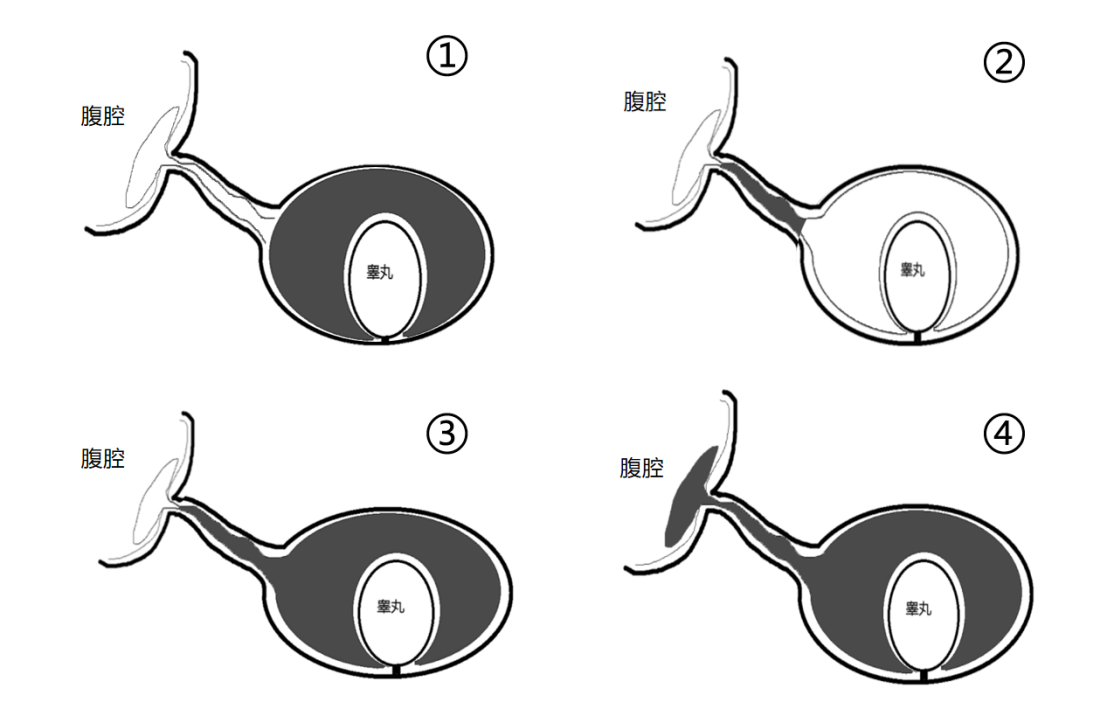

根据鞘状突闭合部位的不同,便将鞘膜积液分为了四种类型,分别是:

①睾丸鞘膜积液:鞘状突闭合正常,睾丸鞘膜囊内有较多积液。

②精索鞘膜积液:也称精索囊肿,鞘状突两端闭合,中间的精索鞘膜囊未闭合,且有积液,与腹腔、睾丸鞘膜囊不相通。

③睾丸精索鞘膜积液:鞘状突在内环闭合,在精索处未闭且与睾丸鞘膜连通,与腹腔不通。

④交通性鞘膜积液:鞘状突完全未闭合,与腹腔相通。

超声表现如图所示: